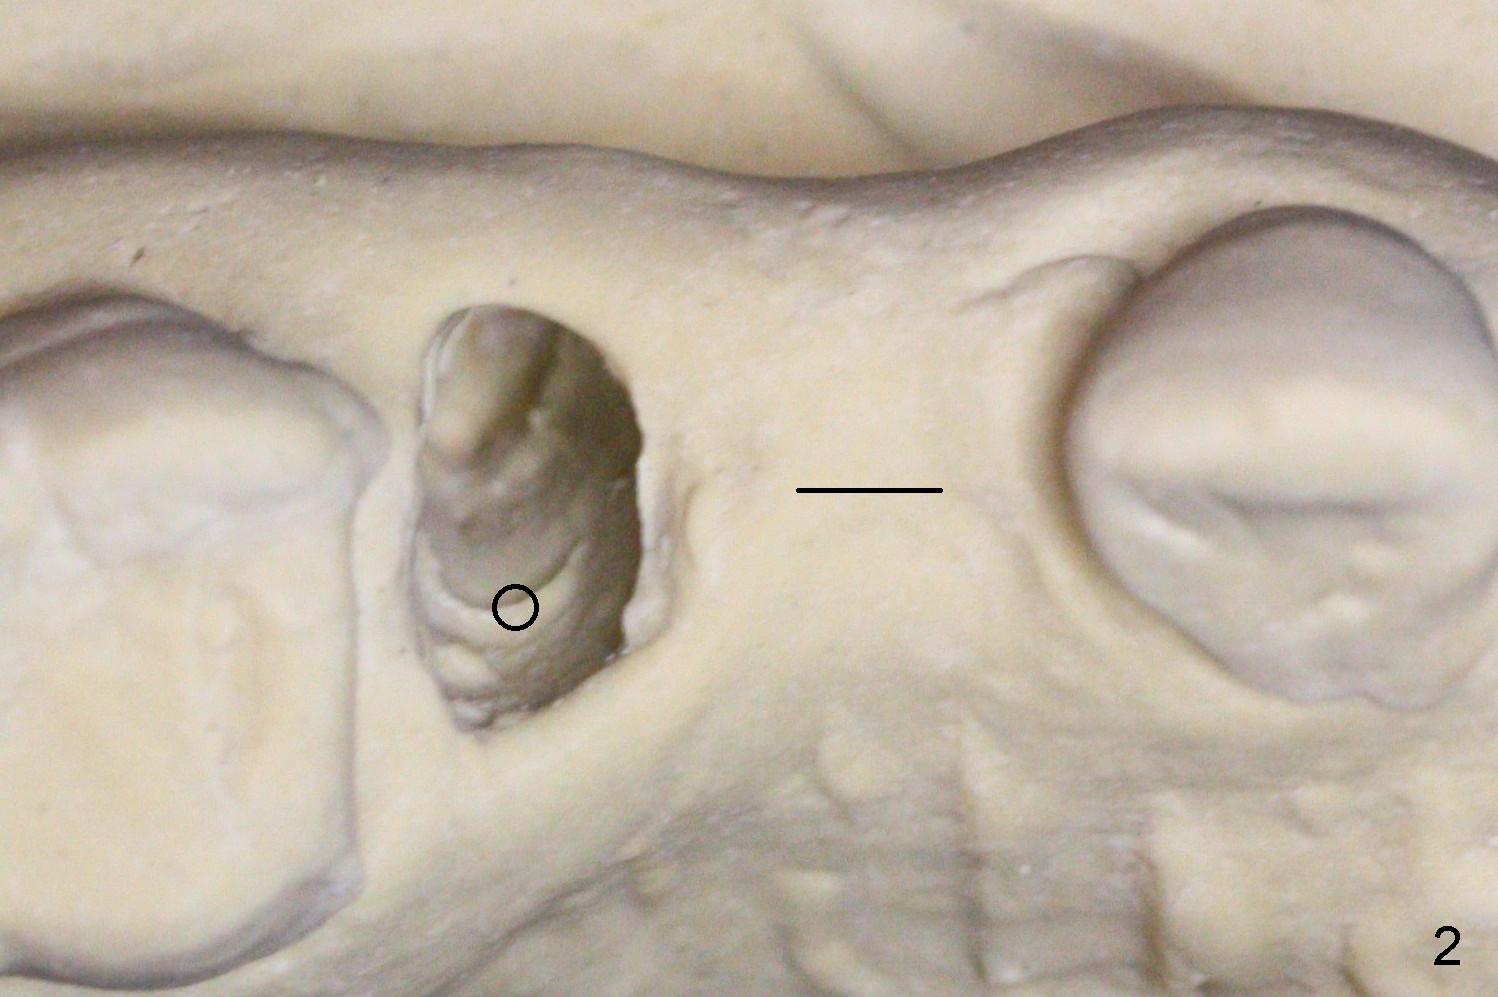

The buccal plate of the socket of #4 is thin and short (Fig.1, 5B (coronal section of the socket) red area) with apical perforation (Fig.5B >). Osteotomy at #4 starts with 1.6 mm drill in the palatal slope (Fig.2 circle; Fig.5C blue arrow), while that at #5 with Magic Split (Fig.2 black line). In fact sinus perforation occurs with the 1.6 mm drill. Osteotomy increases by using Magic Drills sequentially (2.8 and 3.3 mm) at #4 and Magic expander (3.0 mm) and the same Magic Drills at #5 (Fig.3). A 4x11 mm dummy IBS implant is placed with insertion torque of 45 Ncm at #4 with apparently intruding into the sinus (Fig.3). When a 4.5x9 mm implant is placed, the insertion torque is actually reduced (<35 Ncm, Fig.4). As osteotomy or implant diameter enlarges, it shifts buccally with less bone contact buccally (Fig.5D, as compared to Fig.5C)). In brief, once a dummy implant has achieved a reasonably high stability, do not over seat it. A small immediate implant may have more solid bone contact.